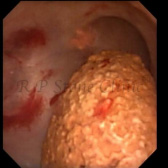

The Images Below are of Kidney Stones taken as snapshots from the video recording of RIRS Surgery done at our hospital with Digital Flexible Ureteroscopes, Flex XC and Flex XC S.